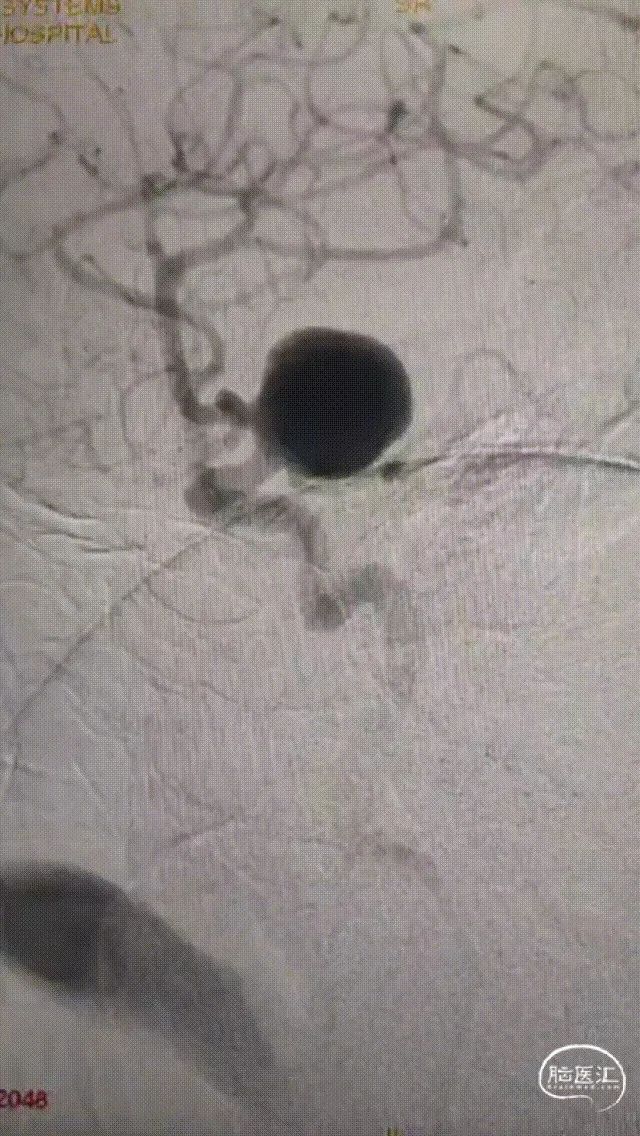

术前影像

脑动脉DSA提示右侧颈内动脉虹吸段巨大动脉瘤。

右侧虹吸段载瘤动脉近端直径为4.13mm,瘤体最宽径为24.2mm,动脉瘤流入、流出道均显示明显迂曲,近端载瘤动脉也有迂曲。病变范围约32mm。